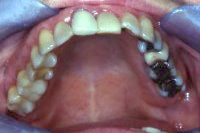

Das Anliegen dieser Patientin war es, ihre alten Amalgamfüllungen ersetzt zu haben. Die alten Amalgame sind in Abb. 1 gut sichtbar. Unser Vorgehen bestand zuerst darin, einen absolut dichten "Non-Latex"-Kofferdam im Mund zu legen, wie es in Abb. 2 gezeigt wird, um zu verhindern, dass Amalgamstücke oder -staub in den Körper gelangen. Die herausgenommenen Amalgamreste werden von uns in sogenannten Amalgamabscheidern gesammelt und müssen als Schwermetall entsorgt oder recycelt werden.

In Abb. 3 ist das Resultat der Behandlung zu sehen. Alle Amalgamfüllungen wurden durch zahnfarbene Kompositfüllungen ersetzt.